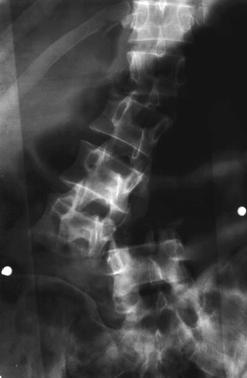

FRACTURA - LUXATIE T12 FRACTURA COMPLEXA DE COLOANA

VERTEBRALA LOMBARA